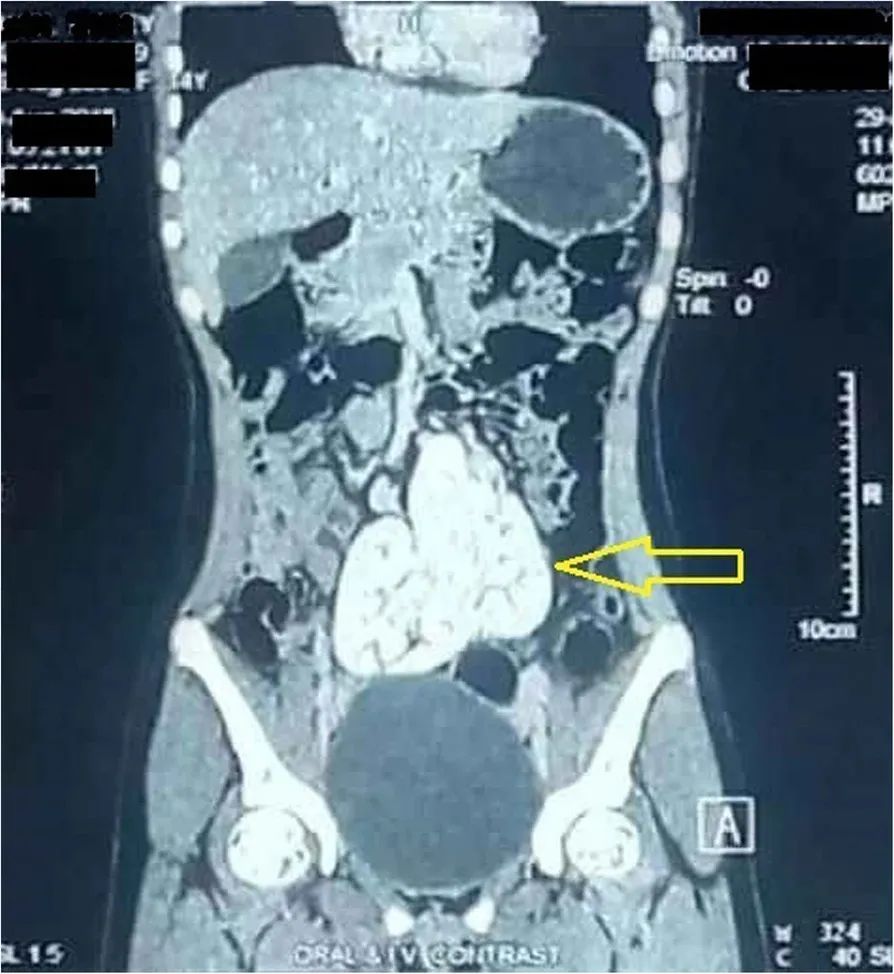

MDCT显示一个圆形肿块,大小约9 cm(垂直)×10 cm(水平),位于盆腔骶骨岬前方。该肿块最终确定为两个异位肾后外侧旋转不良,并在第三、第四和第五腰椎(L3-L5,腹主动脉分叉处下方)中线前方的内侧融合,形成了一个团块肾,能清晰显示血管供应和尿路解剖。